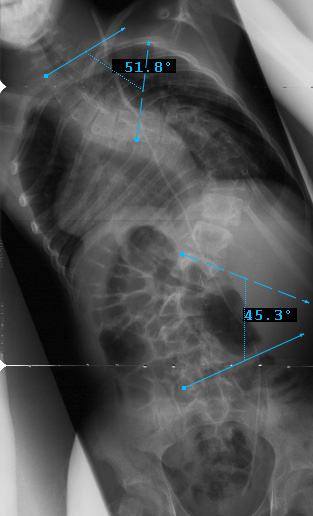

Preop PA View

Preop LEFT Bend

Preop RIGHT Bend